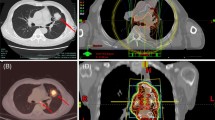

Brickey et al. investigated the role of myeloid differentiation primary response 88 (MyD88) in regulating nuclear factor kappa-B (NF-kB) activating responses and innate immunity in post-radiation lung tissues. They found that MyD88 was instrumental for regulating inflammatory processes that aid in recovery from radiation [55, 64]. The activation of cGMP–AMP synthase–stimulator of interferon genes (cGAS-STING) signaling and ROS/RNS also plays an important role in lung injury mediated by non-infectious inflammatory processes [65, 66]. The major signaling pathways involved in immunotherapy-induced RRP are shown in Fig. 1. The activations and interactions of these inflammatory-related signals also contributed to the therapeutic effects of anti-PD-1/PD-L1, with or without radiotherapy. Anti-PD-1/PD-L1 therapy may have evoked an inflammatory reaction mediated by the lymphocytes, cytokines, and proteins as a result of radiation exposure in patients’ previously irradiated fields (Fig. 2).